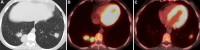

As lung transplantation has become the most effective definitive treatment option for end-stage chronic respiratory diseases, yearly rates of this surgery have been steadily increasing. Despite improvement in surgical techniques and medical management of transplant recipients, complications from lung transplantation are a major cause of morbidity and mortality. Some of these complications can be classified on the basis of the time they typically occur after lung transplantation, while others may occur at any time. Imaging studies, in conjunction with clinical and laboratory evaluation, are key components in diagnosing and monitoring these conditions. Therefore, radiologists play a critical role in recognizing and communicating findings suggestive of lung transplantation complications. A description of imaging features of the most common lung transplantation complications, including surgical, medical, immunologic, and infectious complications, as well as an update on their management, will be reviewed here. Keywords: Pulmonary, Thorax, Surgery, Transplantation Supplemental material is available for this article. © RSNA, 2021.